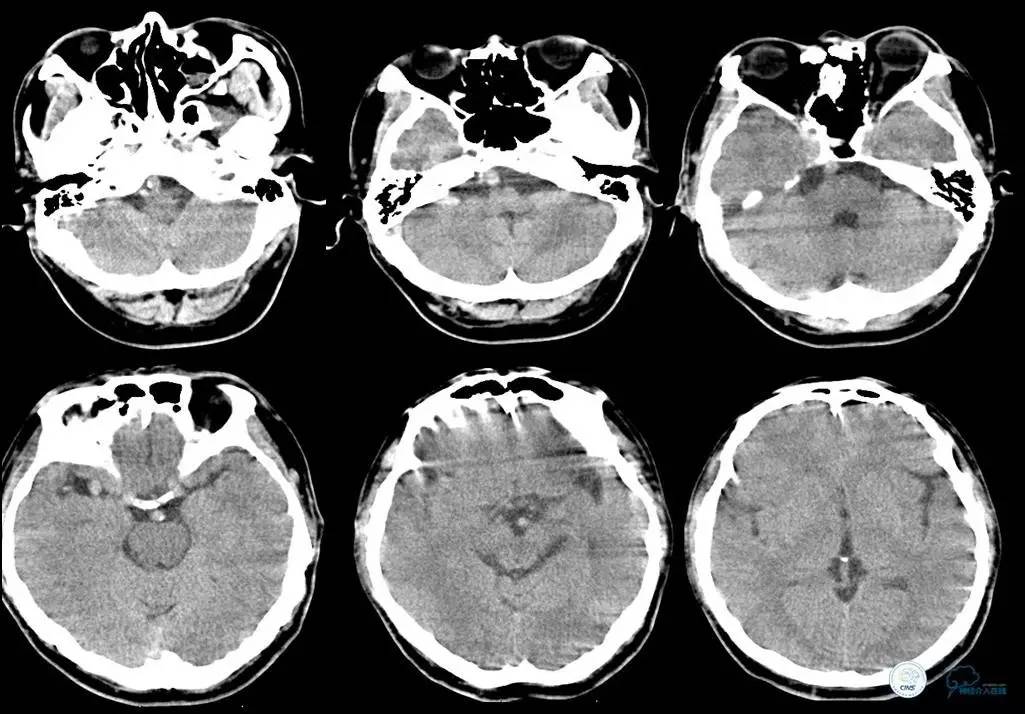

▼头CT

▼心电图:窦性心律,T波异常,心肌缺血改变。

血常规:白细胞为16.45×109/L,中性粒细胞为84.99%。

离子:钾为3.21mmol/L,镁为1.13mmol/L。

血糖:12.3mmol/L。

心肌酶:乳酸脱氢酶为187IU/L,肌钙蛋白、肌红蛋白、CK、CK-MB均正常。

凝血四项:凝血酶原时间为15.3s,活化部分凝血酶原时间为43.0s。

-

2014年12月15日22时50分

患者言语不清、右侧肢体麻木无力等症状缓解,但四肢末端厥冷。心电监护示,SPO2为99%,P为65次/分,R为18次/分,BP为103/60mmHg。T为35.5℃。

初步诊断为短暂性脑缺血发作。追问患者家属病史,入院前曾有大汗,未进食,低血容量性休克不除外。补液纠正休克。